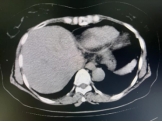

术前影像

介入科团队在CT影像监测与引导下,准确将消融探针插入肿瘤内,将肿瘤组织迅速冷却至-196℃,使癌细胞迅速降温,形成的“冰球”效应能够让医生直观监控,精细控制冷冻范围,确保完全覆盖肿瘤病灶并进行杀伤,冰冻后迅速复温至80℃,导致组织内肿瘤细胞脱水破裂,肿瘤细胞迅速死亡。